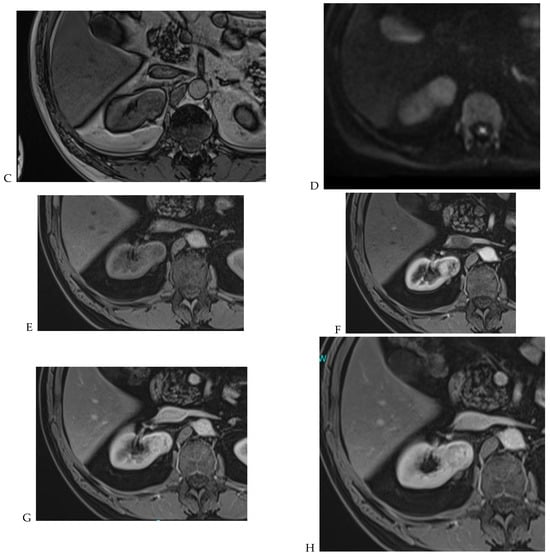

Figure 8.

Same lesion as Figure 3. Chromophobe renal cell carcinoma in the left kidney of a 68-year-old-woman. (A) Axial T2-weighted fast SE image shows the exophytic heterogeneous isointense renal mass with a posterior hyperintense area. Transverse in-phase (B,C) opposed-phase MR images show no significant loss of signal intensity on the opposed-phase image. (D) The ADC map shows restriction of tumor diffusion into the renal mass. Transverse nonenhanced (E) and gadolinium-enhanced T1-weighted gradient-echo spoiled MR images in (F) corticomedullary, (G) nephrographic, (H) and delayed phase images show a mid-intense enhancement of the lesion without visible washout.